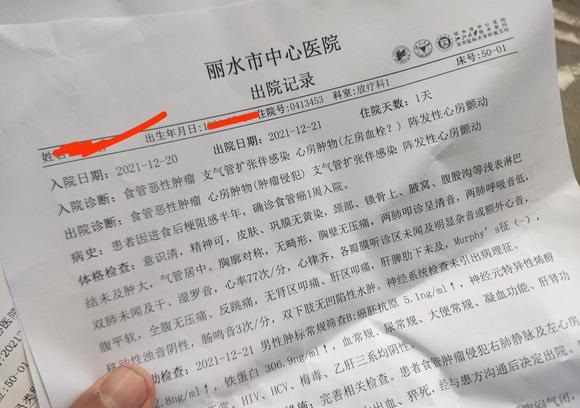

为自己,拼一次 02021-12-22 患者

为自己,拼一次 02021-12-22 患者 -